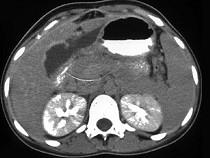

问题 女,45岁,急性右上腹剧痛2小时,向右肩放射,影像检查如图,应诊断为 ( )

选项 A.急性胆囊炎 B.慢性胆囊炎 C.胆囊穿孔 D.胆囊腺肌增生症 E.胆道梗阻

答案 C